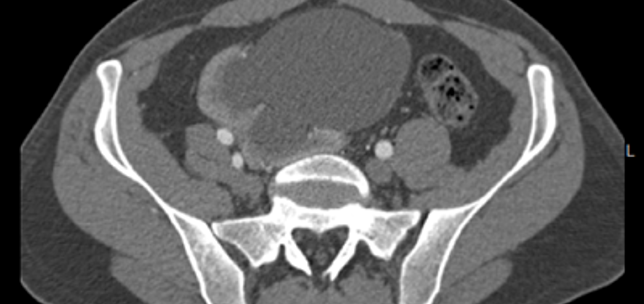

Uroradiology